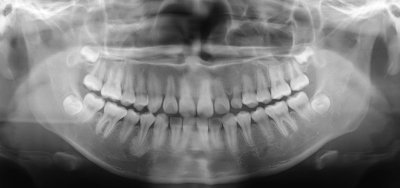

15歳の男子。かかりつけ歯科医のエックス線検査で右側の下顎小臼歯部に異常を指摘され、精査を希望して来院した。自覚症状はないという。初診時のエックス線写真とCTを別に示す。

疑われるのはどれか。1つ選べ。